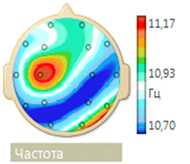

Electroencephalogram (EEG) showed epileptiform activity. An irregular alpha rhythm with a peak frequency of 10.5 Hz is recorded on the patient's EEG. The frequency-spatial structure of the alpha rhythm is pathologically distorted. The structure of the maximum values of average coherence is represented as a triangle in fronto-central departments, which is characteristic of an active epileptic process. A moderate increase in low diffuse beta and theta activity is noted. Against this background, in the left frontotemporal region, epileptiform activity in the form of spikes is recorded in large numbers, the frequency of which reaches 30 per minute. Rare discharges of high, sharp, bilaterally synchronous alpha waves with a frequency of 1-2 per min (Figure 1 & 2).

Figure 1 Pathological inversion of the frequency-spatial structure of the alpha rhythm (the minimum frequency values are located not in the frontal, but in the parietal regions).